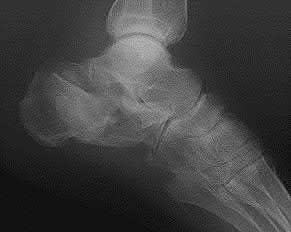

A 35 year-old female presents after prolonged extrication from a motor vehicle collision complaining of severe pelvic pain. Physical examination reveals diminished perianal sensation. She is otherwise neurologically intact. Figures A through D are radiographs and representative CT cuts of her injury. Which of the following nerve roots has likely been injured by the acute trauma?

The clinical scenario is consistent with a high-energy sacral fracture. The radiographs in figures A and B demonstrate a sacral fracture with posterior displacement of the right hemipelvis seen on the inlet view. Figures C and D are axial and sagittal CT images which show a displaced fracture of the right

hemisacrum along with a transvere fracture component through the S3 body . Diminished perianal sensation is concerning for an S2 nerve root injury.

Mehta et al reviewed the current management of sacral fractures. They note that the S1 and S2 nerve roots are more likely to be injured with sacral fractures as they occupy 1/3 to 1/4 of the neural foramina, as opposed to S3 and S4, which only occupy 1/6 of the neural foramina.

Robles reviewed the current literature to ascertain principles of evaluation and treatment for transverse sacral fractures. The author notes that injury to nerve roots S2 to S5 is manifested by impairment of urinary and anal continence and sexual function.

The first illustration demonstrates the sacral nerve root dermatomal distribution. The second shows a pelvic cadaver dissection demonstrating the sacral nerve roots as they exit the foramina.